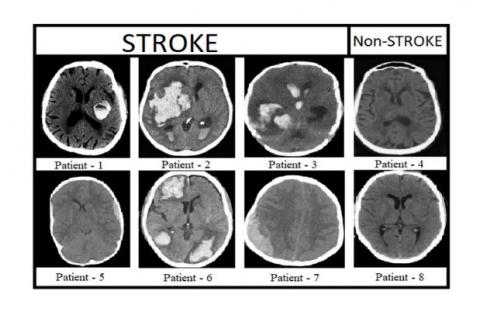

Figure 9 shows the pre-processed brain CT images of 8 patients, in which 6 patients are affected with stroke and remaining 2 are non-stroke patients. Figure 10 shows the labeled brain CT images of 8 patients. These labeled images contain three classes represented with white, gray, and black colors. Patients 4&8 are not affected with stroke, so these images are labeled with only two classes. The images shown in Figure 11 are predicted by our proposed model. Figure 12 shows output images of our proposed stroke segmentation on brain CT images.

Figure 10. Labeled images of stroke and non-stroke patients